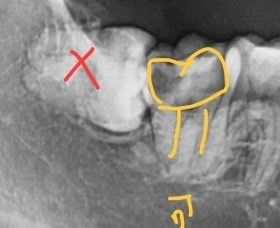

오른쪽 하단 제2대구치 썩은정도 좀 봐주세요

이 정도면 신경치료해도 예후가 안좋을 정도로 많이

썩은거라고 볼 수 있나요? 발치하는것이 맞을지 신경치료를 하는것이 나을지 모르겠습니다

이정도면 사랑니 발치하고 신경치료 해볼만 합니다 다만 100% 성공한다는 보장은 못하고요 그냥 아무것도 안해보고 뽑기엔 아까운 치아네요

사진으로 봤을 경우 치아의 충치가 너무 많이 진행된것으로 보입니다. 이런경우에는 충치를 제거하면서 노출된 신경을 치료하고 보철치료를 해야 합니다

가능하면 신경은 살려서 사용할수 있도록 하는것이 좋을것으로 생각됩니다.